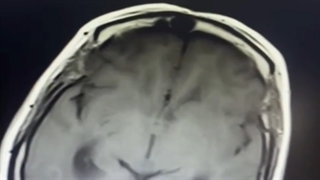

نورالژی عصب سه قلو سمت راست